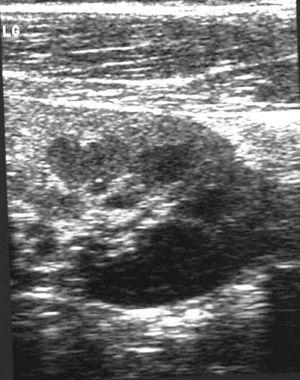

Paciente de 12 años que inicia con dolor cólico en región subcostal y flanco izquierdo; tras 24 h de evolución, presenta fiebre de 38 °C sin otra sintomatología. En la ecografía abdominal se objetiva una lesión hipoecogénica en tercio inferior de RI que correspondía a una NA (fig. 1). Se inicia tratamiento con cefotaxima. El paciente continúa febril, con persistencia del dolor y elevación de los reactantes de fase aguda, todos los urocultivos y hemocultivos son negativos. Se añade cloxacilina al cuarto día del ingreso, al objetivar una lesión cutánea en el maléolo interno izquierdo, con aspecto séptico, secundaria a una epidermólisis ampollosa de base. Se detecta al sexto día en la auscultación pulmonar crepitantes en la base izquierda. Pese a haberse realizado una radiografía que fue normal el día del ingreso, se realiza un control en el que se objetiva una condensación retrocardíaca izquierda. Se replantea el diagnóstico y se realiza una TC en el que se objetiva imagen compatible con nefronía de 2 cm en el polo inferior del RI y un absceso de 1 cm en el polo superior (fig. 2). Mantiene fiebre durante 7 días. Se sustituye la cefotaxima por ceftazidima con la que completa 10 días de tratamiento y se añade eritromicina durante 7 días y completa 21 días con cloxacilina oral. La ecografía se normaliza a los 26 días. La gammagrafía a los 6 meses de la infección descarta cicatrices renales.

Figura 1. Ecografía renal por fiebre sin foco con dolor abdominal: imagen sugestiva de nefronía, consistente en área hipoecogénica en labio posterior.